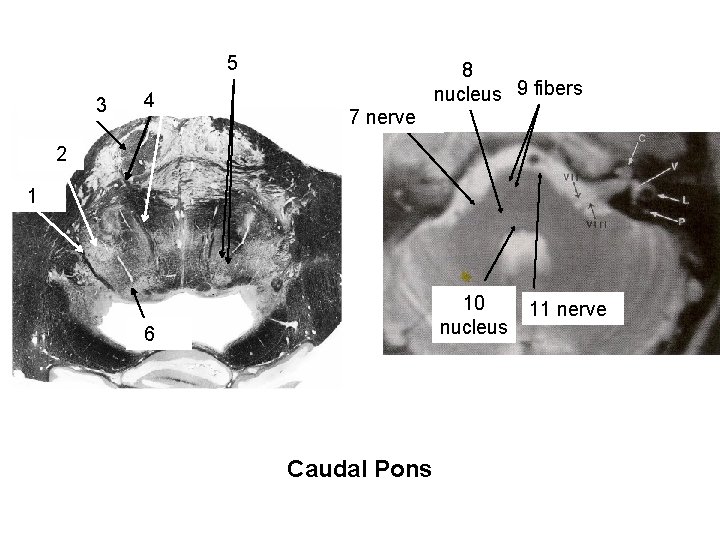

Reticular formation with reticular nuclei & descending rubrospinal fibers 5 descending cortical fibers 3 abducens nerve roots 4 8 descending 9 fibers nucleus cortical fibers facial nucleus exit of facial 7 nerve roots facial nucleus 2 Facial nerve roots 1 abducens exit of VI nerve nucleus roots 10 nucleus abducens nucleus 6 Caudal Pons 11 nerve